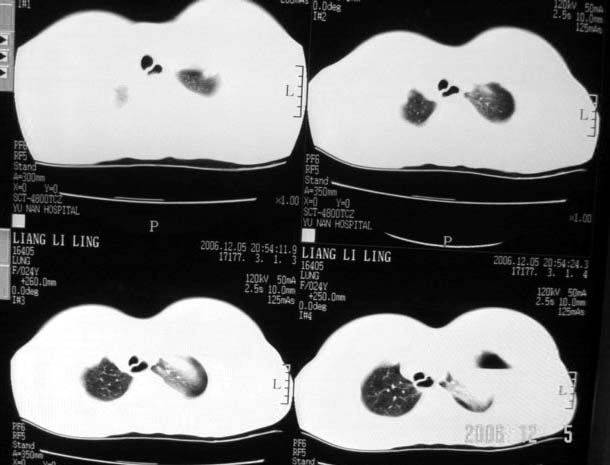

标题: CT5517:女性、24岁,反复胸痛、气促不能平卧半月。

左肺可见二个含气或液气的囊状影,左肺段支气管、左肺动脉显示不清,纵隔右移,考虑:左肺支气管肺囊肿,左肺发育不良,纵隔疝。

我看这是膈疝,在纵隔窗第六\\七幅图像上可见胃粘膜影,再者可见两个腔影,这在液气胸是不会有的.

支持膈疝,纵隔窗内可见消化道的内容物。